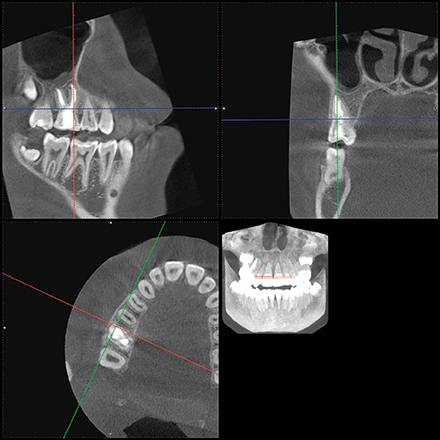

The location of the roots of the maxillary right dentition closely proximate the buccal and palatal cortical plates of the alveolar processes, which were thin particularly at the canine and first premolar with thicker cortex regions lateral to the second premolar and first molar (Figs. 4-7).

Fig. 5 Fig. 6

Fig. 7 Fig. 8